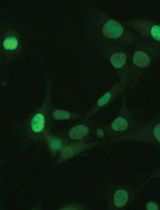

The subretinal layer between retinal pigment epithelium (RPE) and photoreceptors is a region involved in inflammation and angiogenesis during the procession of diseases such as age-related macular degeneration. The current protocols of whole mounts (retina and RPE) are unable to address the intact view of the subretinal layer because the separation between retina and RPE is required, and each separate tissue is then stained. Non-separate Sclerochoroid/RPE/Retina whole mount staining was recently developed and reported. The method can be further combined and optimized with melanin bleaching and tissue clearing. Here, we describe steps of both non-pigmented and pigmented mouse Sclerochoroid/RPE/Retina whole mount including eyeball preparation, staining, mounting and confocal scanning. In addition, we present the confocal images of RPE, subretinal microglia and the neighboring photoreceptors in Sclerochoroid/RPE/Retina whole mounts.

The retina in eyes is surrounded by retina pigmented epithelium (RPE), choroid and sclera. Generally, in whole mount staining, the retina tissue is separate from the choroid/RPE, and each part of the separate retina and choroid/RPE is stained. Thus, the separate whole mount staining of either retina or choroid/RPE does not address integral subretinal information. Recently, a Sclerochoroid/RPE/Retina whole mount protocol was developed (Kim et al., 2016; Ye et al., 2020). The method allows us to observe the integral and intact subretina as well as the neighboring RPE and photoreceptors. The method is also applicable to examine choroidal neovascularization from the choroid to the photoreceptor layer, but there is still a limitation in laser penetration depth of confocal microscopes, restraining the application of this protocol in animals with large eyes, which could be countered by use of light-sheet fluorescence microscope (Renier et al., 2014). Here, we illustrate the details of whole steps for immunofluorescent staining and mounting procedure of Sclerochoroid/RPE/Retina using mouse eyeballs.